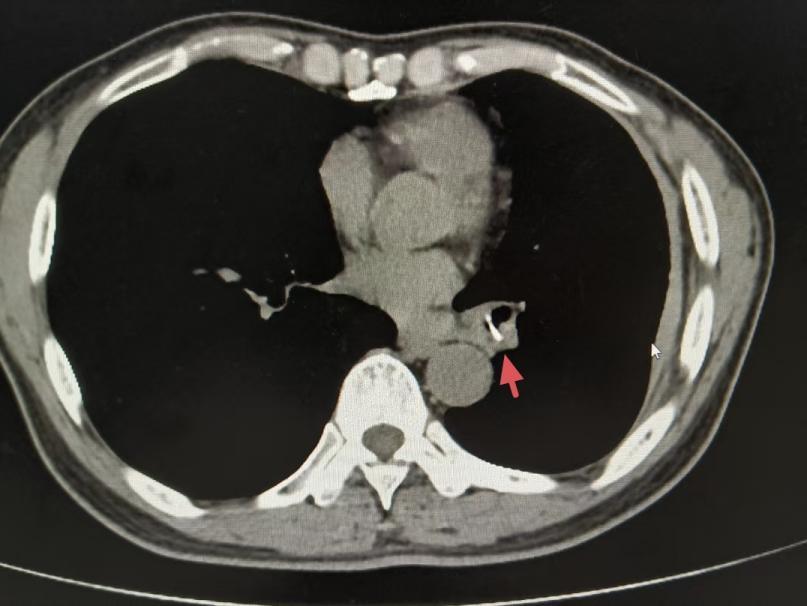

在市十二医再次接受的胸部CT结果显示,陈叔左下肺支气管有可疑异物影像。追问病史时,陈叔回忆起一年前吃鱼时曾有剧烈呛咳史,但当时症状自行缓解。呼吸科副主任医师陈子谓敏锐地捕捉到了这一关键信息,随后的纤维支气管镜检查也印证了他的猜想。镜下清晰可见一块疑似骨头的异物嵌顿于左下肺支气管,周围组织已形成化脓性炎症。困扰陈叔一年多的罪魁祸首终于现形。

经抗感染治疗控制局部炎症后,3月27日,该院呼吸科团队为患者实施纤维支气管镜异物取出术。在麻醉团队精准施麻支持下,术中患者呛咳反应轻微、生命体征平稳,主刀医生手持支气管镜快速探过声门、气管、左主支气管,抵达左下叶基底段开口处见一片“块状鱼骨”嵌顿在亚段支气管内,但不规则鱼骨易划伤黏膜、部分骨块软化,嵌顿位置狭窄、炎症水肿等均为手术增加难度。

历时20分钟,一块大小约1.3x1.5cm的不规则鱼骨被成功取出。术后陈叔咳嗽咳痰症状显著改善,术后三天即康复出院。